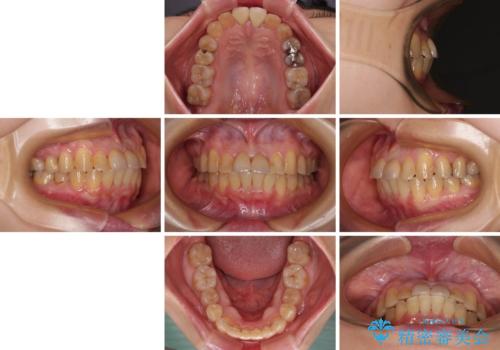

前歯のデコボコをワイヤー矯正できれいに整える

- 前歯のデコボコと変色した前歯を気にして来院された患者様です。

抜歯矯正により口元を引っ込めることも検討しましたが、特に口元の突出感は気になっていないとのことで、非抜歯にてワイヤー装置で矯正治療を行うこととしました。

気になっていた前歯の変色も、矯正治療後にオールセラミッククラウンにて補綴治療を行うこととしました。

舌の突出癖により治療期間中に開咬となり、治療が長引きましたが、口元も治療前よりも引っ込めることができ、すっきりとした仕上がりとなりました。